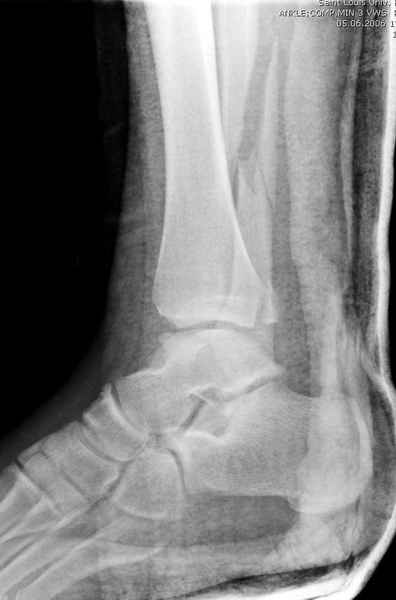

>На сделанных у нас снимках видно, что не все благополучно...

Неравномерность суставной щели может быть связана с разрывом глубокой порции дельтовидной связки и ротацией м/берцовой кости за счет поврежденных структур синдесмоза(репозиция ее на уровне перелома как-будто удовлетворительная).

По моему мнению,ассиметрия суставной щели обусловлена импрессией медиальной части суставной поверхности б/б кости. Да, позиционный винт здесь не лишен, но через 4 недели целесообразность его проведения сомнительна, брейс, ограничение осевой нагрузки достаточно.Есть еще деонтологические аспекты повторной операции, не все так плохо выполнено предыдущим доктором!

Импрессия медиальной части суставной поверхности бывает при супинационном механизме перелома лодыжек (тип А по классификации АО). Здесь механизм пронациия+наружная ротация (тип С, синдесмоз и межкостная мебрана повреждены),

перелом медиальной лодыжки отрывной, при этом в 20-30% бывает повреждение дельтовидной связки.

Мое мнение, что никакой ротации малоберцовой кости здесь нет и синдесмоз тоже впорядке. Все дело в некачественно репозиции медиального мыщелка. Скорее всего его или немного ротировали при операции или сместили латерально. Более склонен ко второму варианту.

Расширенная медиальная щель более чем на 4 мм и укорочение малоберцовой более чем 2 мм, а перелом заднего края большеберцовой смещения более 2мм с вовлечением 30% поверхности сустава, считается отходом от нормы голеностопного сустава, и подлежит к оперативному вмещательству.